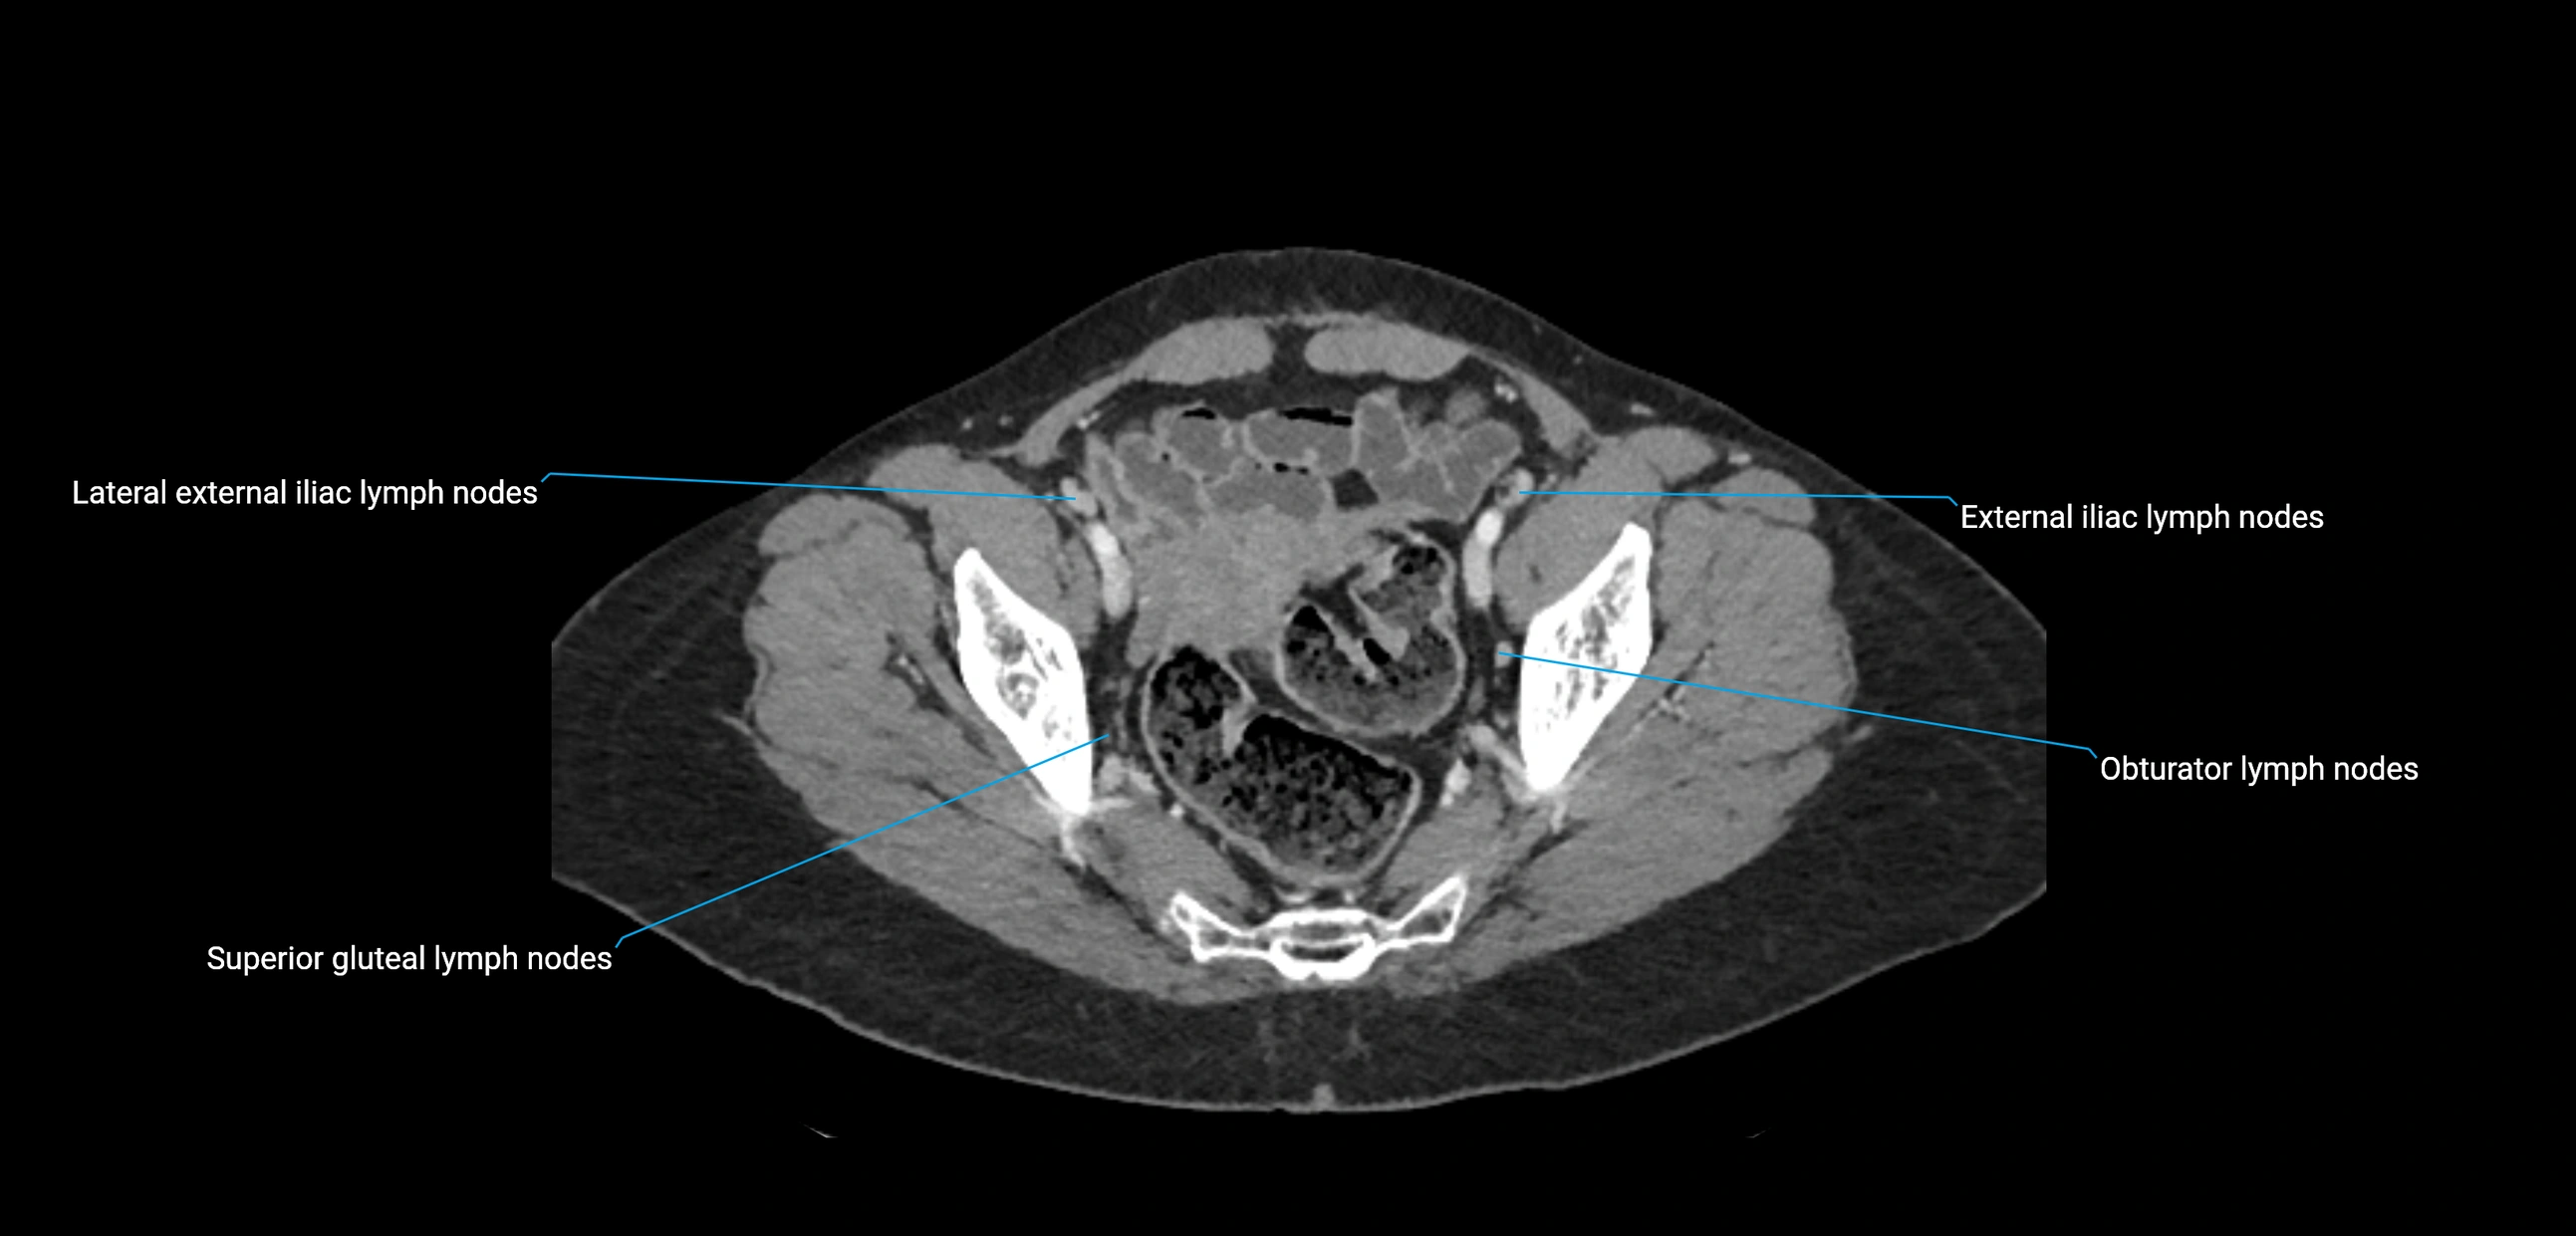

CT image

image